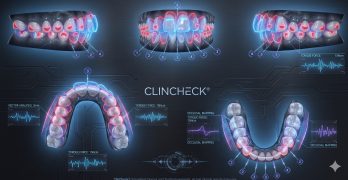

Clase II y Overjet Extremo: Cuando los Alineadores son la Solución Conservadora Ideal.

El artículo presentamos hoy es un caso clínico de una mujer de 42 años que acudió a consulta con una maloclusión … [Leer más...] acerca de Clase II y Overjet Extremo: Cuando los Alineadores son la Solución Conservadora Ideal.